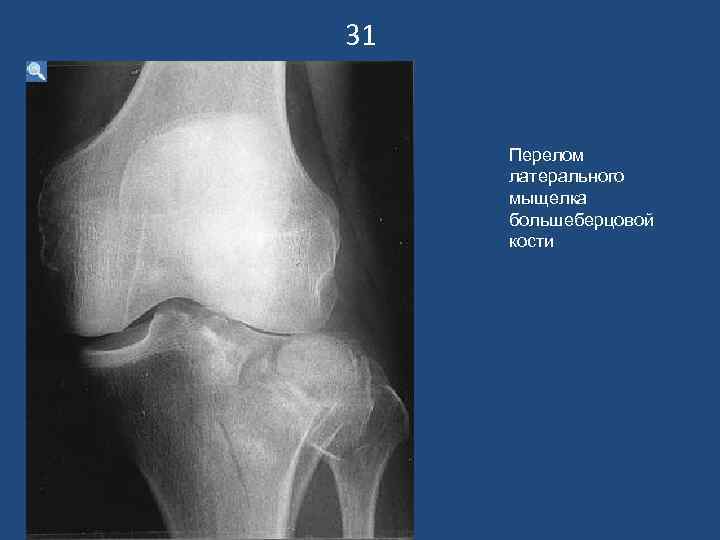

31 Перелом латерального мыщелка большеберцовой кости